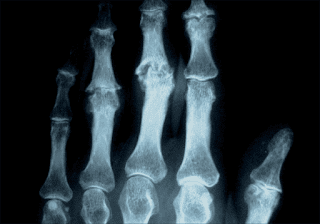

Figura 5. Artrosis nodular de manos. Con quistes subcondrales y perdida parcial del alineamiento articular.

- Osteofitos: proliferaciones óseas en las zonas marginales. Representan el hallazgo radiológico más específicos de la artrosis.

- Quistes subcondrales o geodas: aparecen entre las trabéculas del hueso subcondral sometido a presión. Propias de artrosis muy evolucionadas. Figura 5

- Luxaciones articulares y/o alteraciones del alineamiento óseo: ocurren por remodelación del contorno articular, también propias de la enfermedad avanzada. Figura 5